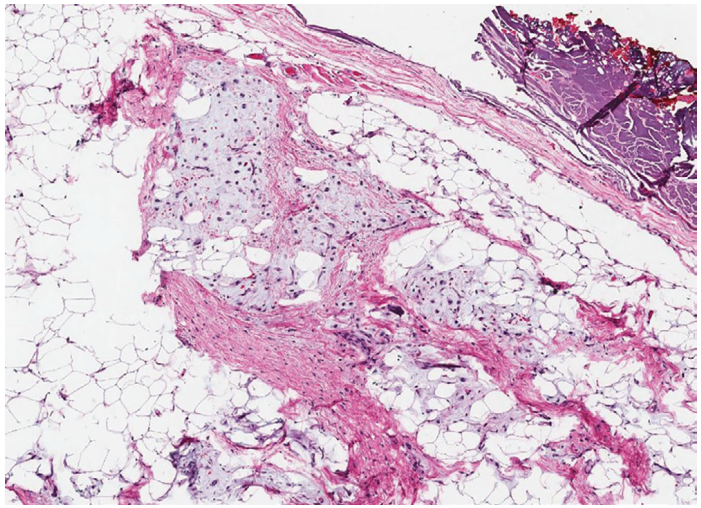

【镜下特征】脂肪母细胞瘤的特征是成熟度不同的脂肪细胞结节嵌入轻度黏液样变基质中,并被不同厚度的纤维间隔隔开(图1)。脂肪细胞成熟可能代表某种程度上的区域性成熟,从原始间叶细胞到印戒样脂肪母细胞,从多空泡样脂肪母细胞(multivacuolated lipoblasts)到成熟脂肪细胞。背景黏液样基质通常表现为薄壁丛状血管,类似于黏液样脂肪肉瘤(图2)。偶尔可以看到异源性成分,如软骨样化生、髓外造血和慢性炎症。没有明显的细胞异型性或核分裂象。

图1:脂肪母细胞瘤是一种边界清楚的、分叶状肿瘤,有厚度不等的纤维间隔。